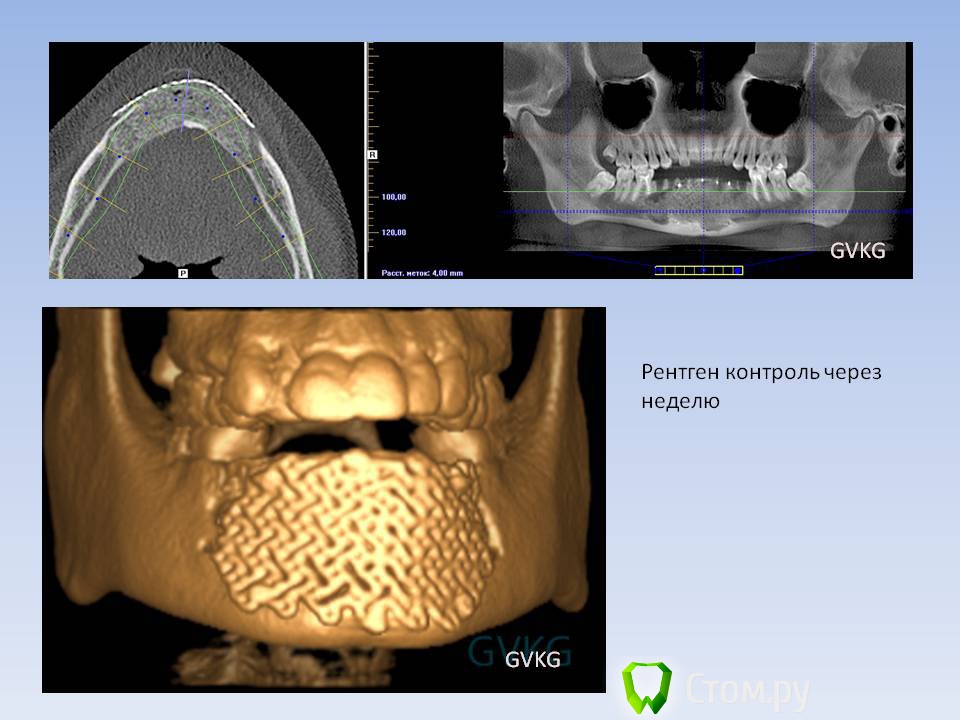

ПалСаныч Опубликовано 15 ноября, 2013 Поделиться Опубликовано 15 ноября, 2013 тут вот намедни сделал похожий случай: случайная находка при санации полости рта. При цитологическом исследовании пунктата новообразования цитограмма кисты. 18 Ссылка на комментарий

ПалСаныч Опубликовано 16 ноября, 2013 Поделиться Опубликовано 16 ноября, 2013 у 46 зуба выстоял медиальный корень, мы депульпировали и 35 и 46, а выстоящую верхушку 46 резецировали. 1 Ссылка на комментарий

ПалСаныч Опубликовано 16 ноября, 2013 Поделиться Опубликовано 16 ноября, 2013 (изменено) Ольга Викторовна, если Вы чуть повнимательнее прочитаете моё сообщение, то в первой строчке вы найдете результат цитологического исследования))) Должны быть очень веские причины, чтобы мы выполняли операцию без какого либо морфологического исследования. У этого пациента невозможно было выполнить первично гистологическое исследование, так как стенка кисты была очень тонкая и при пункции получили прозрачную опалесцирующую жидкость. Чтобы получить ткань необходимо было продырявить эту полость, поскоблить по стенкам, отправить на гистологическое исследование, неделю его ждать. Что в принципе при наличии клинической картины, рентгенологического и цитологического исследования делать нецелесообразно. После операции, естественно любой материал направляется на гистологическое исследование. А, и еще, про какое воспаление Вы говорите? что то я не понял. Олег, про мембранайзинг не знал, часто видел как используется на форуме и решил что это наш местный слэнг))) Если правообладатель не против, то в этом сообщении я оставлю как есть, но нигде более обещаю не использовать)))) Если необходимо исправить, то по первому требованию выполню. Ну и конечно, спасибо всем за оценку))) Кстати, на счёт морфологического исследования: весьма интересная и редкая (во всяком случае для наших гистологов) - при гистологическом исследовании выявлена киста с элементами амелобластомы. Вот такая вот штукенция. Изменено 16 ноября, 2013 пользователем ПалСаныч 5 Ссылка на комментарий